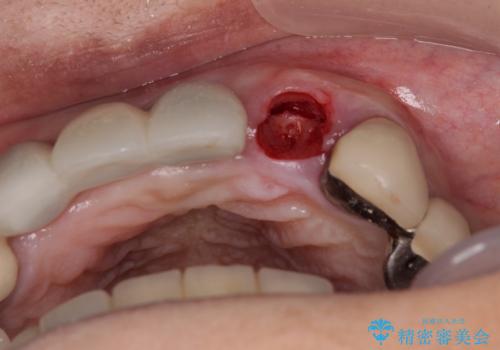

歯根周辺の骨や歯肉の状態は良く、抜歯して速やかにインプラントを埋入し、即日で仮歯を装着するプランにて治療を行うこととしました。

初回カウンセリング時にはセラミッククラウンが装着されていましたが、インプラント治療でのご来院時には前歯は外れて紛失をしてしまったとのことでした。

事前に仮歯の型取りをして用意をしていたため、インプラント埋入後に速やかに仮歯を装着しました。